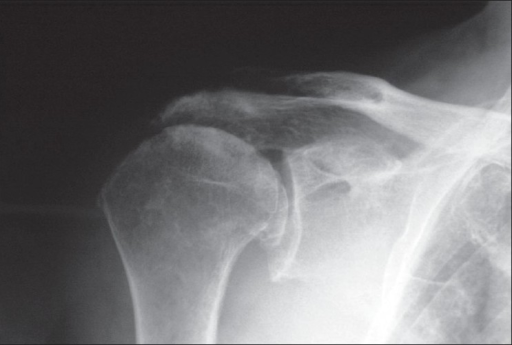

Osteoarthritis

• Osteoarthritis of the shoulder is much less common in comparison to osteoarthritis of the hips or knees